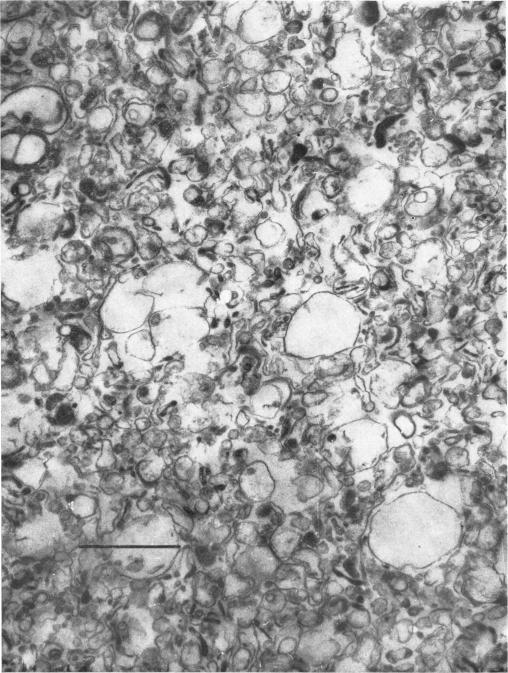

来自实验性肉芽组织的质膜。

Plasma membranes from experimental granulation tissue.

1. A procedure was developed for the preparation of plasma membranes from experimental granulation tissue of the rat without the addition of enzymes. The yield is better than 20% and the purification at least tenfold. 2. Values are given for the activities of 5'-nucleotidase, Na-+, k-+-activated Mg-2+dependent adenosine triphosphatase and leucine beta-naphthylamidase, for lipid composition, and for the gel-electrophoretic patterns of proteins and glycoporteins in the membrane preparations. 3. The plasma membranes from the mature granulation tissue contain proportionally more protein in the lipid phase, but the specific activities of 5'-nucleotidase and Na-+,K-+-activated Mg-2+-dependent adenosine triphosphatase are smaller than in the proliferating tissue. Certain differences were repeatedly observed in the gel-electrophoretic patterns of the developmental phases. 4. The plasma membranes from the granulation tissue were compared with those from rat peritoneal macrophages and from embryonic-chick tendon cells.

1. 开发了一种在不添加酶的情况下从大鼠实验性肉芽组织制备质膜的方法。产率高于20%,纯化倍数至少为10倍。2. 给出了膜制剂中5'-核苷酸酶、钠钾激活的镁依赖型三磷酸腺苷酶和亮氨酸β-萘胺酶的活性值、脂质组成以及蛋白质和糖蛋白的凝胶电泳图谱。3. 成熟肉芽组织的质膜在脂质相中蛋白质比例更高,但5'-核苷酸酶和钠钾激活的镁依赖型三磷酸腺苷酶的比活性低于增殖组织。在发育阶段的凝胶电泳图谱中反复观察到某些差异。4. 将肉芽组织的质膜与大鼠腹膜巨噬细胞和胚胎鸡肌腱细胞的质膜进行了比较。